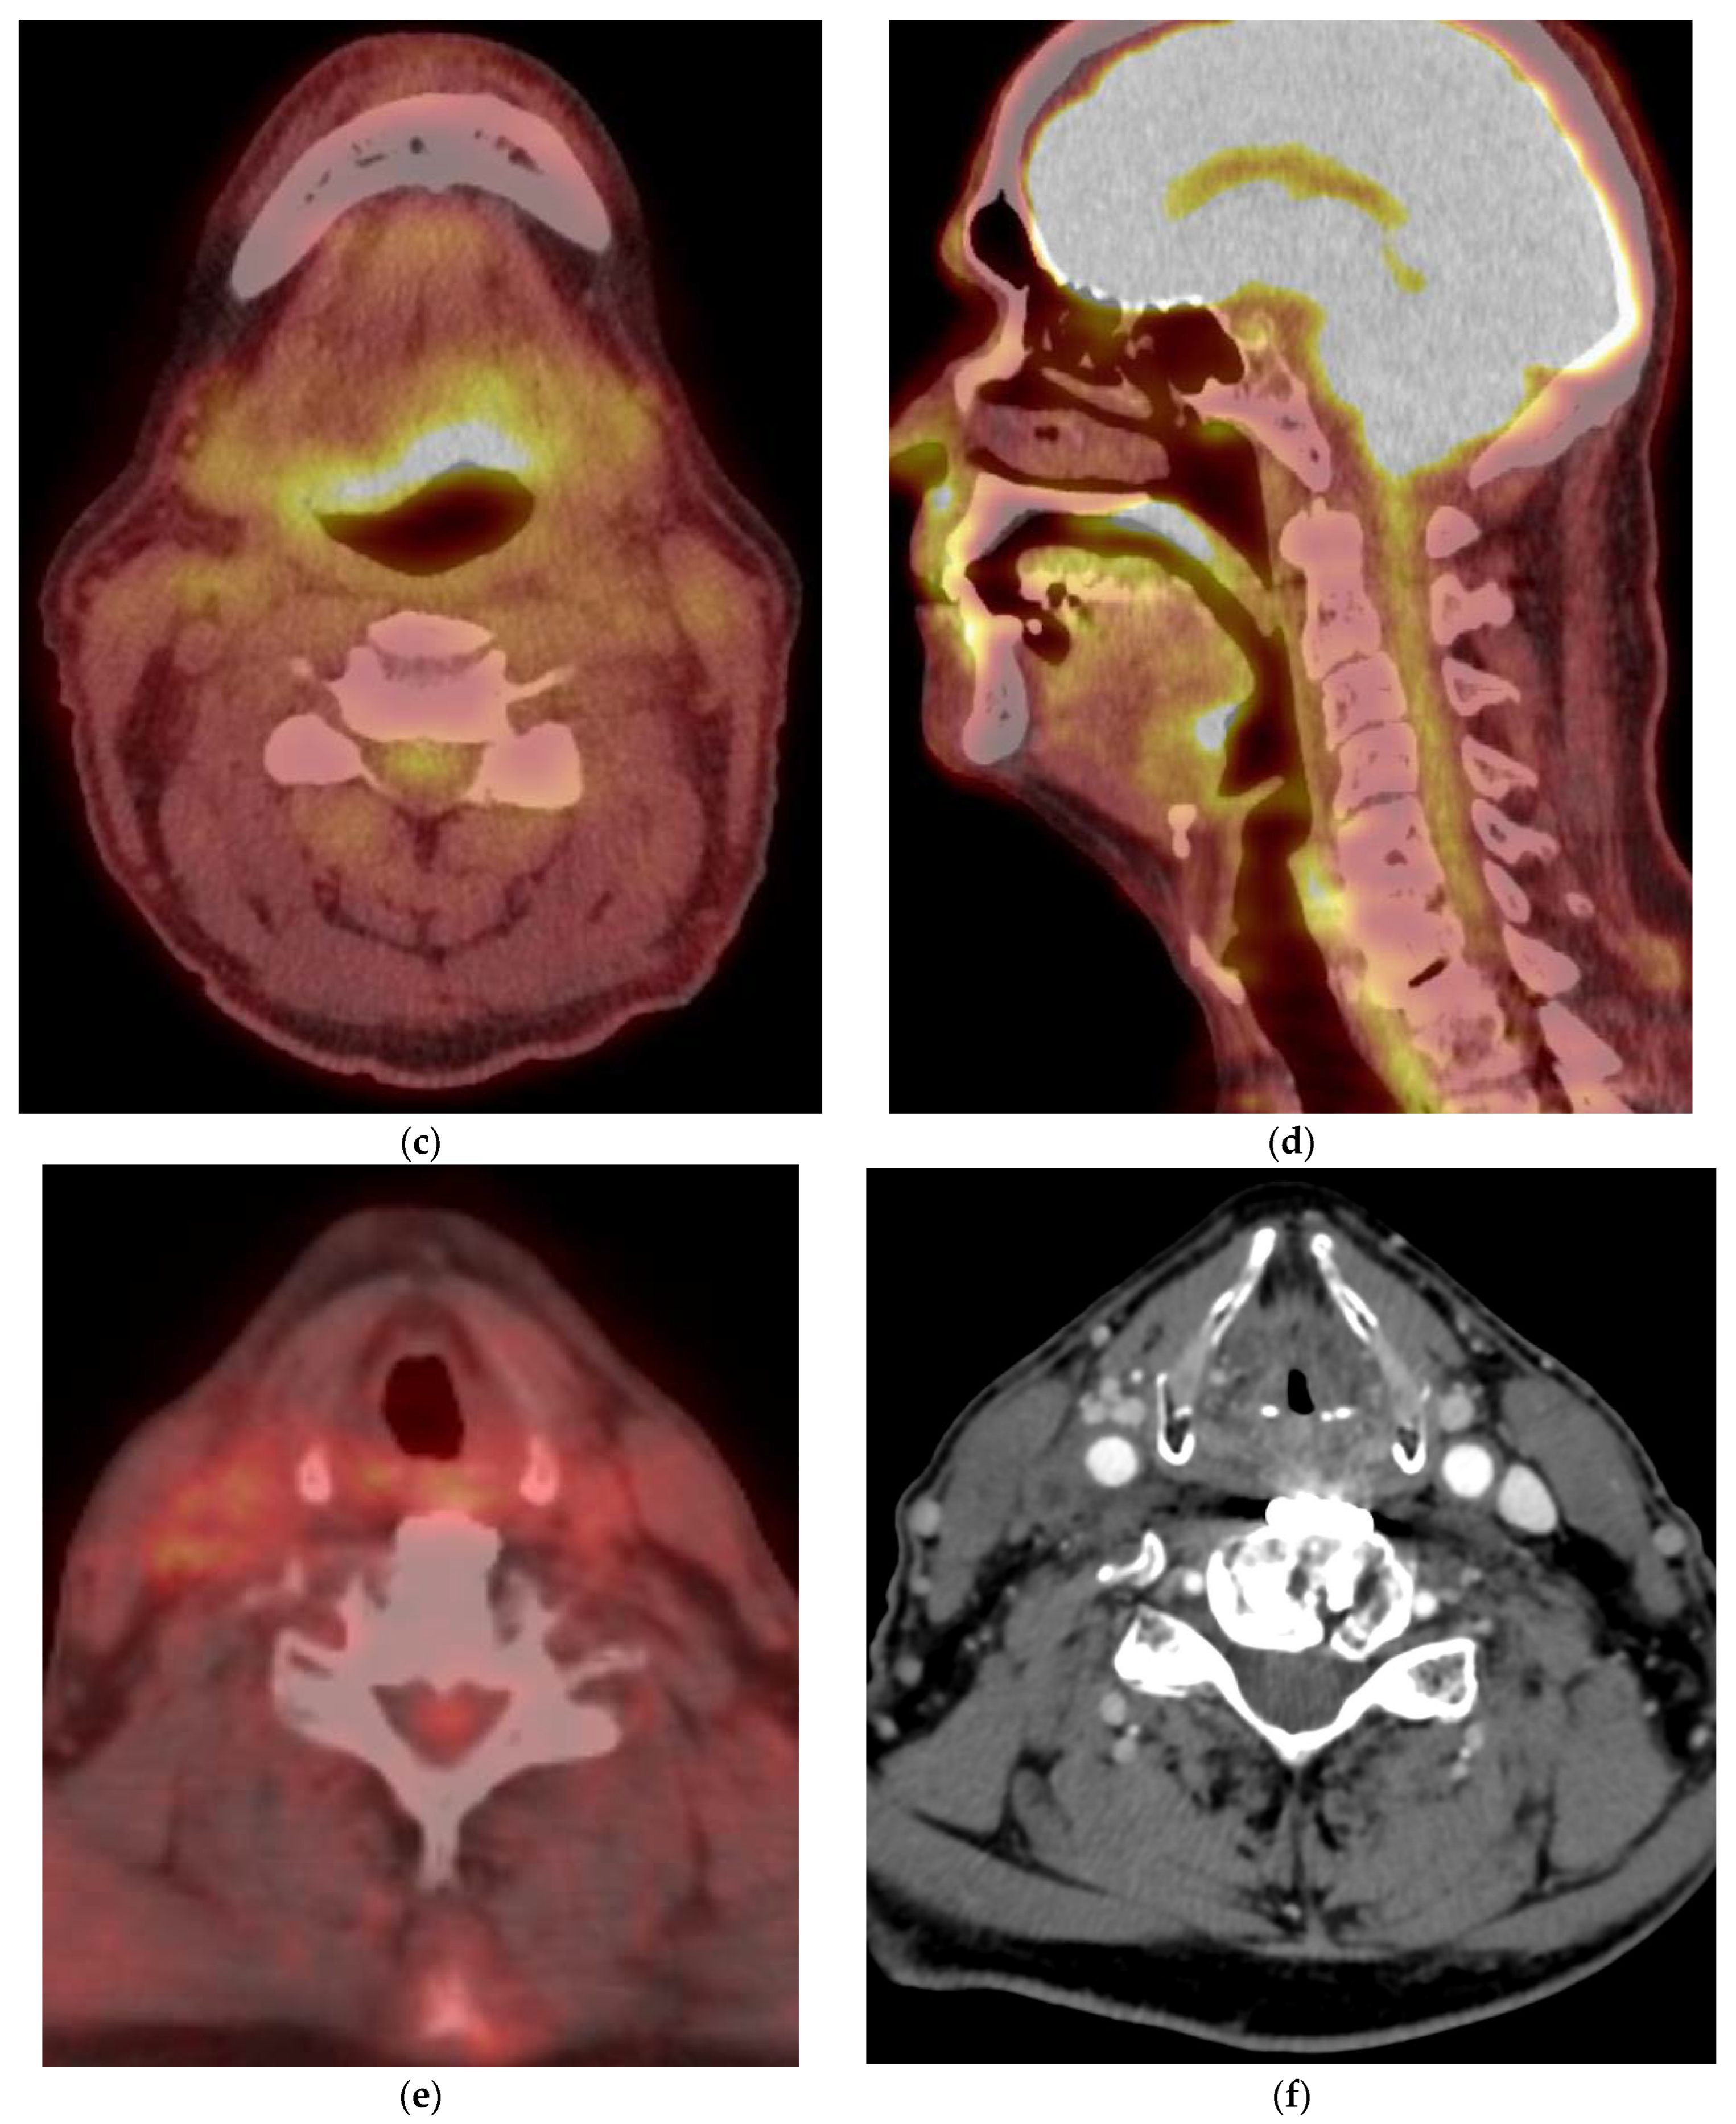

8.2. Response Assessment

9. Disease Monitoring